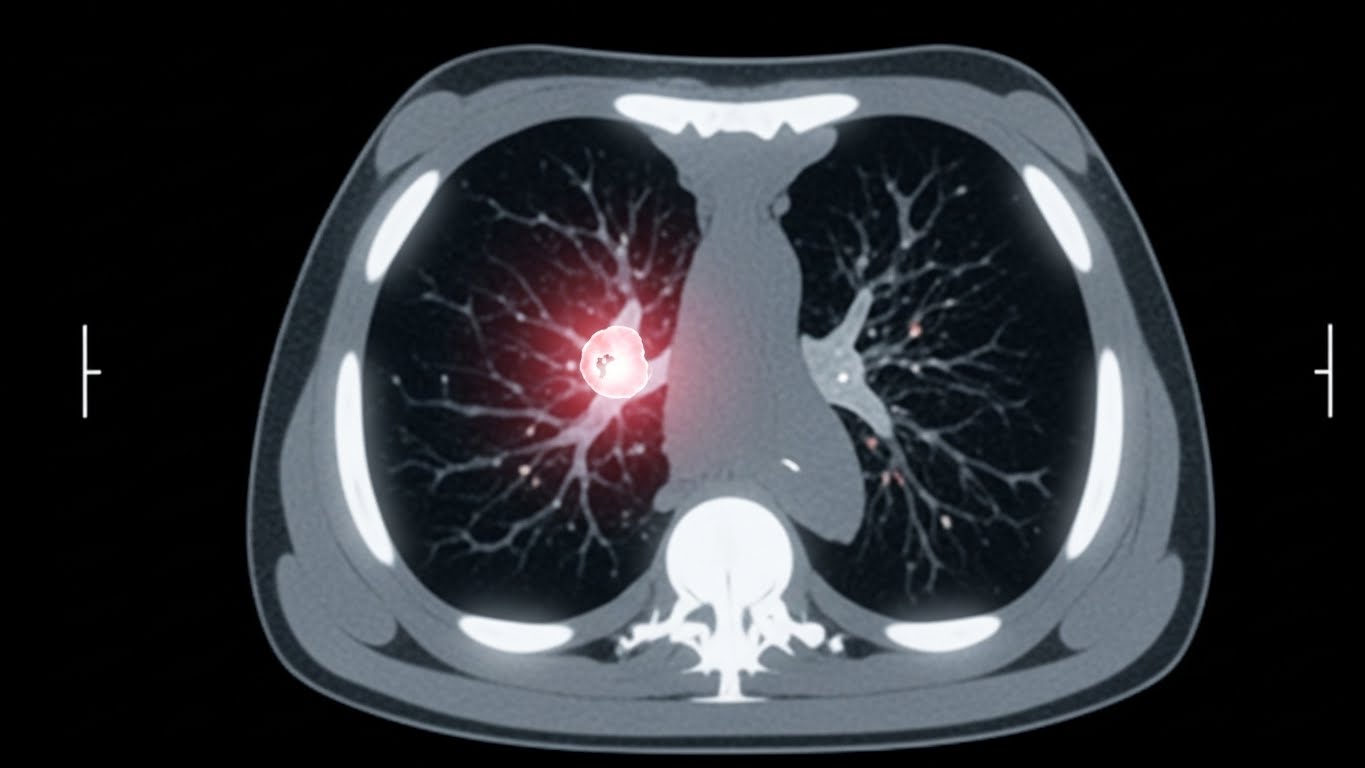

흉부 X-레이에서 이상 소견이 발견되거나, 폐암이 강하게 의심되는 경우에는 추가적인 정밀 검사가 필요합니다. 가장 일반적으로 시행되는 검사는 저선량 흉부 CT입니다. CT는 X-레이보다 훨씬 정밀하게 폐 내부를 들여다볼 수 있어 작은 병변도 놓치지 않고 발견하는 데 큰 도움을 줍니다.

이 외에도 객담 세포 검사, 기관지 내시경 검사, 경피적 폐 생검 등을 통해 암세포의 유무와 종류를 확진하게 됩니다. 이러한 검사들은 다소 불편할 수 있지만, 정확한 진단을 위한 필수적인 과정이므로 의료진의 지시에 따라 적극적으로 임하는 것이 중요합니다.

- 정확한 진단을 위해 흉부 CT, 기관지 내시경 등 정밀 검사를 적극적으로 고려해야 합니다.

A3: 고위험군(장기 흡연자 등)의 경우, 저선량 흉부 CT 검사가 폐암 조기 진단에 가장 효과적인 검진 방법으로 권고됩니다. 일반적인 흉부 X-레이로는 작은 폐암 병변을 발견하기 어려울 수 있습니다. 전문의와 상담하여 본인에게 적합한 검진 계획을 세우는 것이 중요합니다.